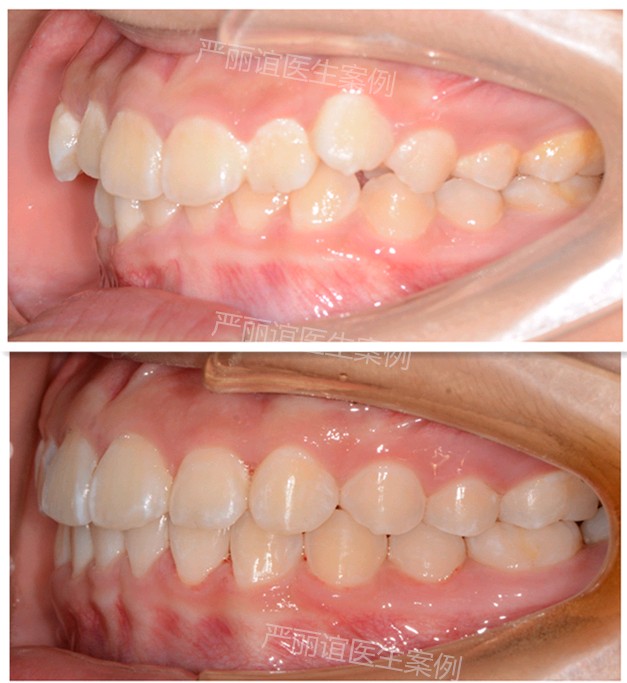

这个患者上颌两个小虎牙外凸,下颌一个畸形过大牙,自觉很影响颜值,想通过矫正改善。

检查发现她上颌最后还有一定的骨量,加上两个小虎牙外凸不是特别严重,需要2-3mm就可以排齐。下颌的畸形过大牙外面的保护层比其他牙齿厚,沟通后选择了上颌推磨牙远移,下颌片切的矫治方案。

一年半时间,矫正结束前后对比图如下。